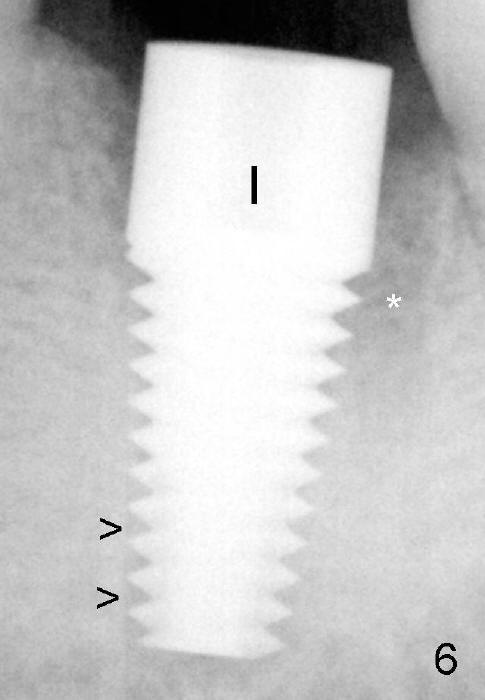

An implant with the same dimension (7x17) mm is placed with insertion torque more than 60 Ncm (Fig.6 I). *: remaining distal socket

Osteo-integration occurs 7 months postop (Fig.10 >, as compared to Fig.6).